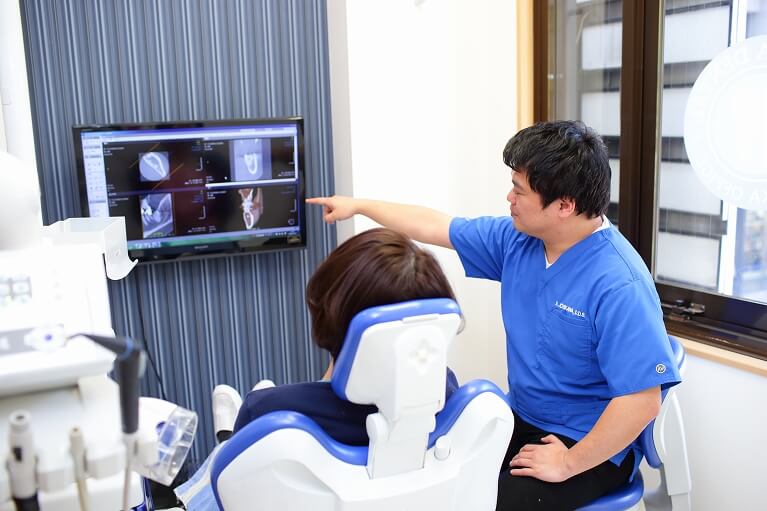

診査と治療の計画

歯が何本失われているか、インプラントを埋め込む顎の骨の大きさや質、位置によって、様々な治療の選択肢があります。

歯が何本失われているか、インプラントを埋め込む顎の骨の大きさや質、位置によって、様々な治療の選択肢があります。

歯に力のかかる方向や強さ、患者様の負担にならない衛生管理方法などを含め、様々な視点から検討をした上で、患者様に最適な治療計画が立てれらます。